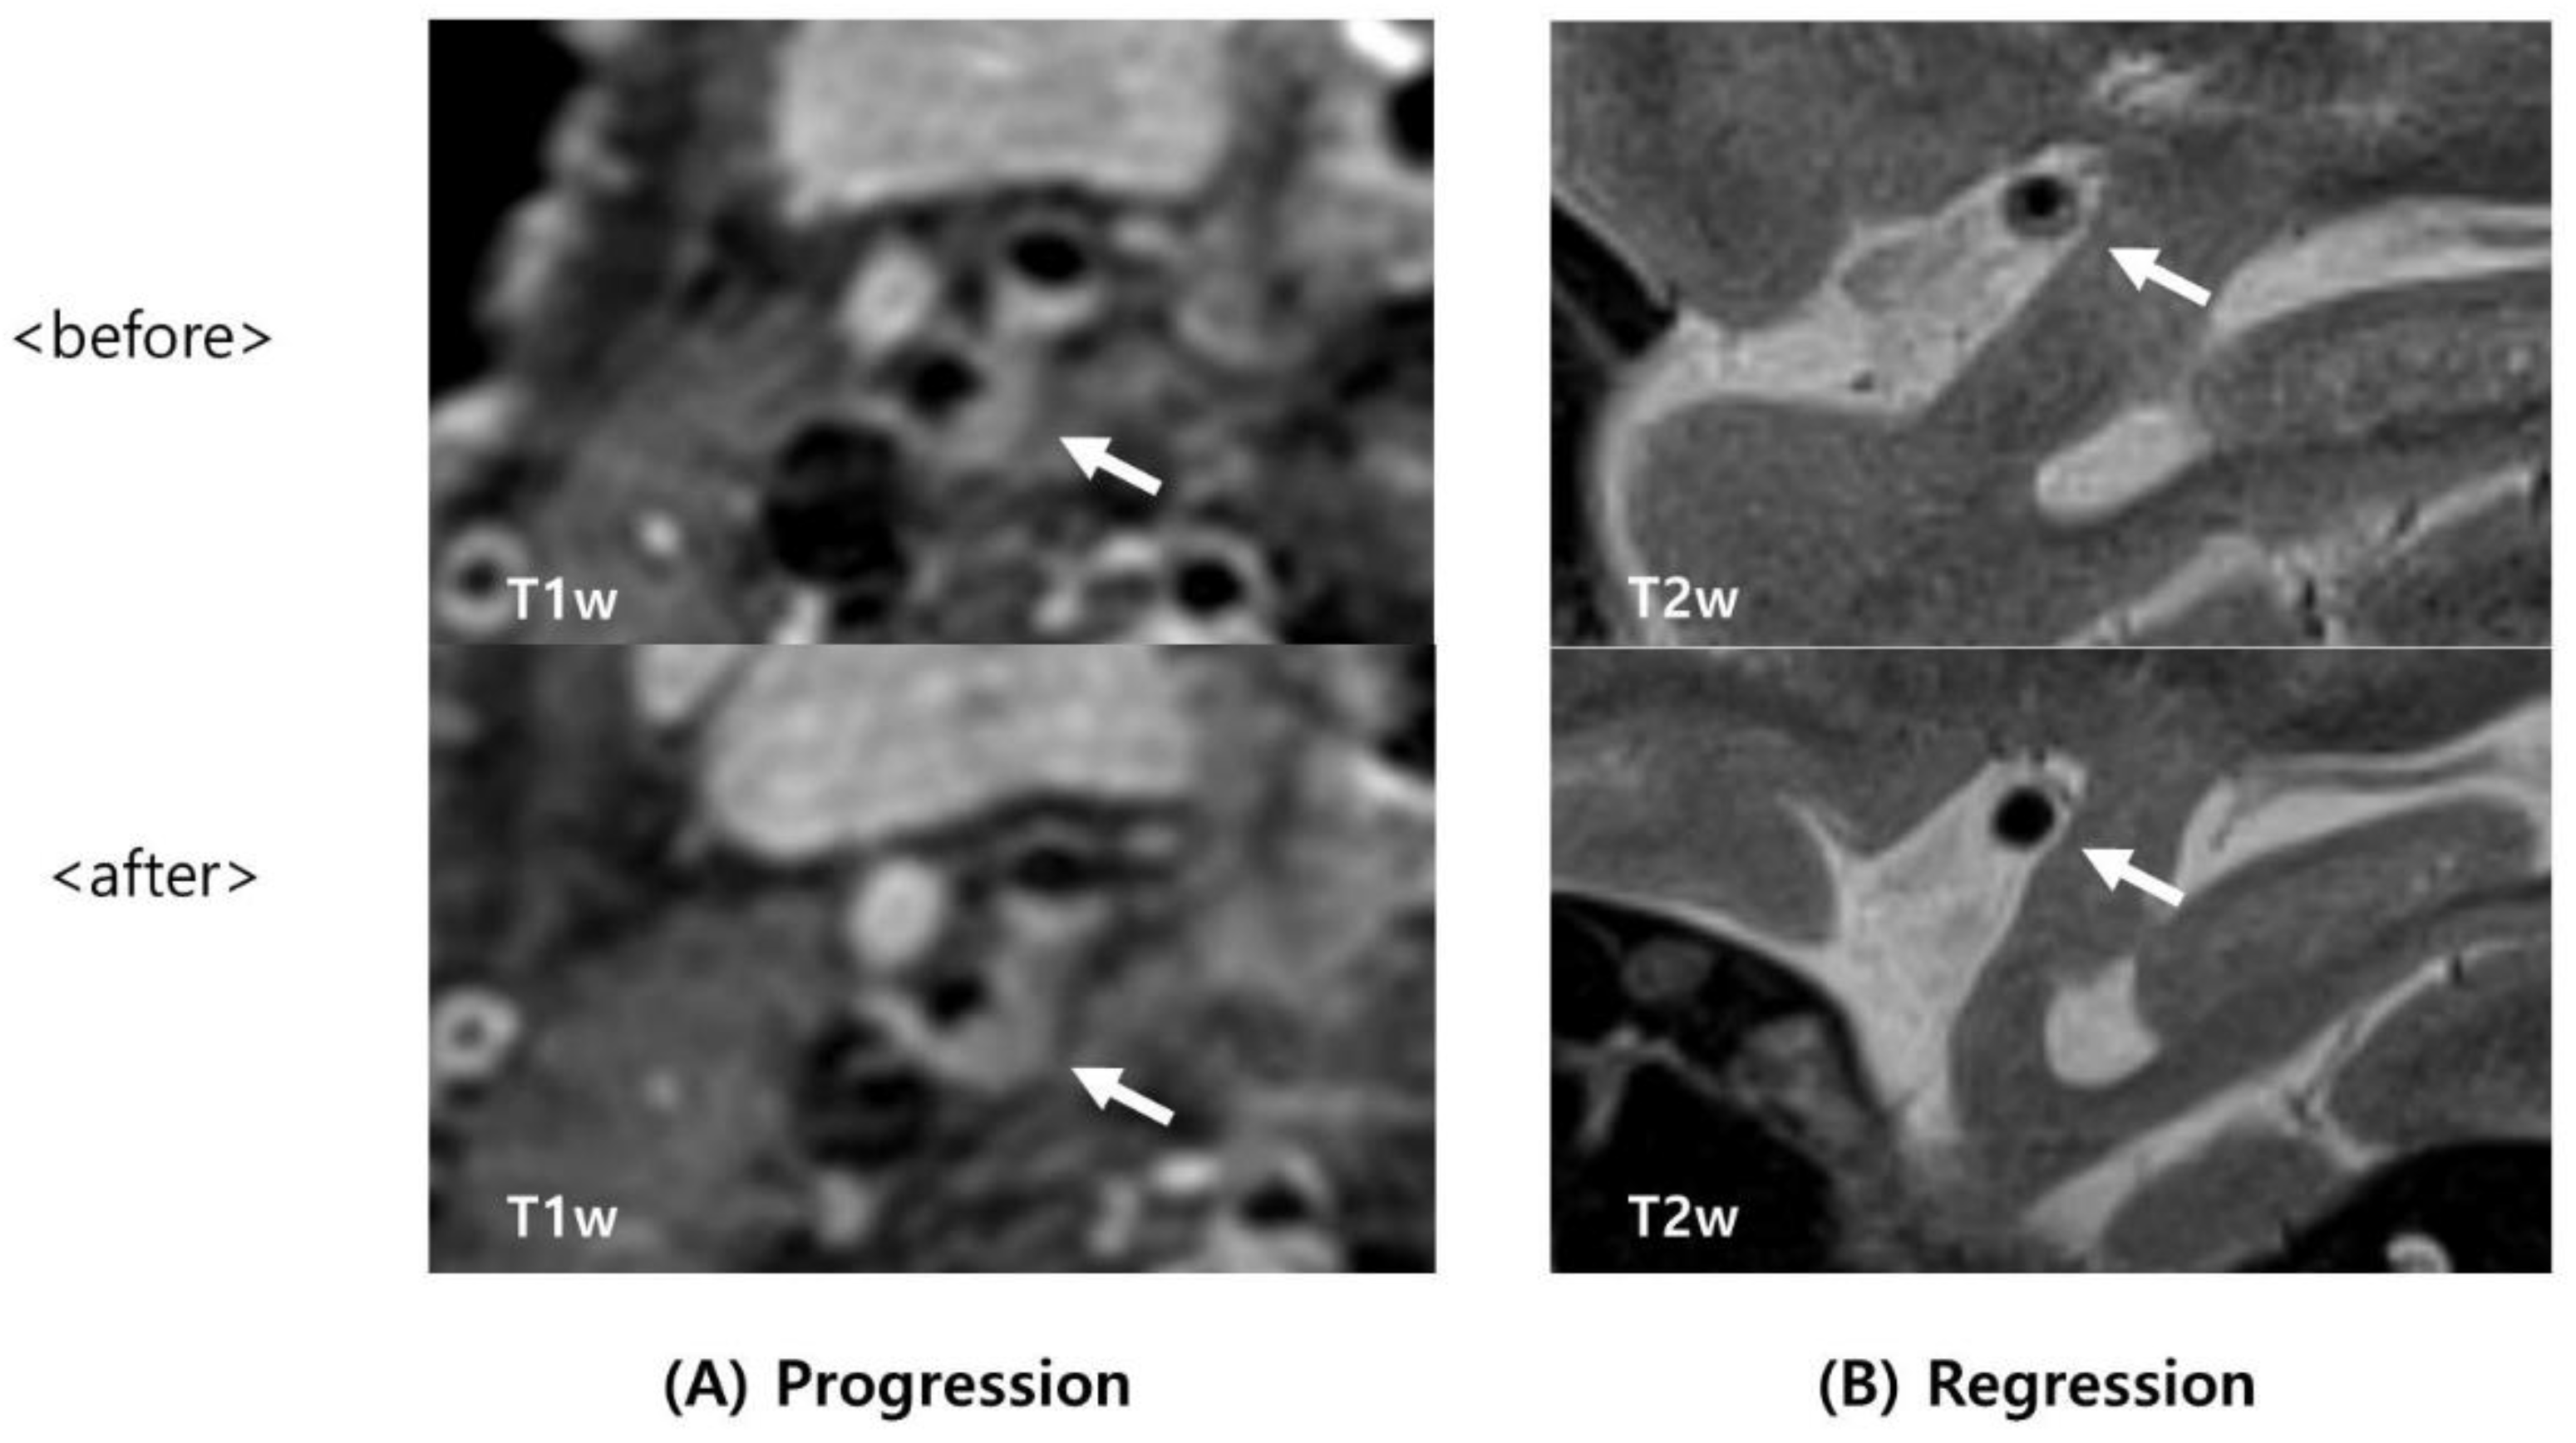

2.4. Image Analysis